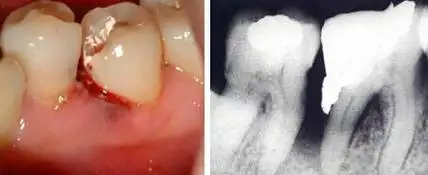

牙颌骨骨髓炎的症状图

如果有牙髓炎和根尖周炎,就需要接受根管治疗.何时需要根管治疗?